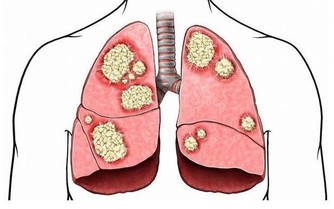

嚴重的甚至會在幾個月後發生中毒性肝病表現,

黃疸、肝臟腫大、肝區疼痛、脾大、腹水、下肢浮腫及肝功能異常,

還可能出現心臟擴大、肺水腫,甚至痙攣、昏迷等症狀。